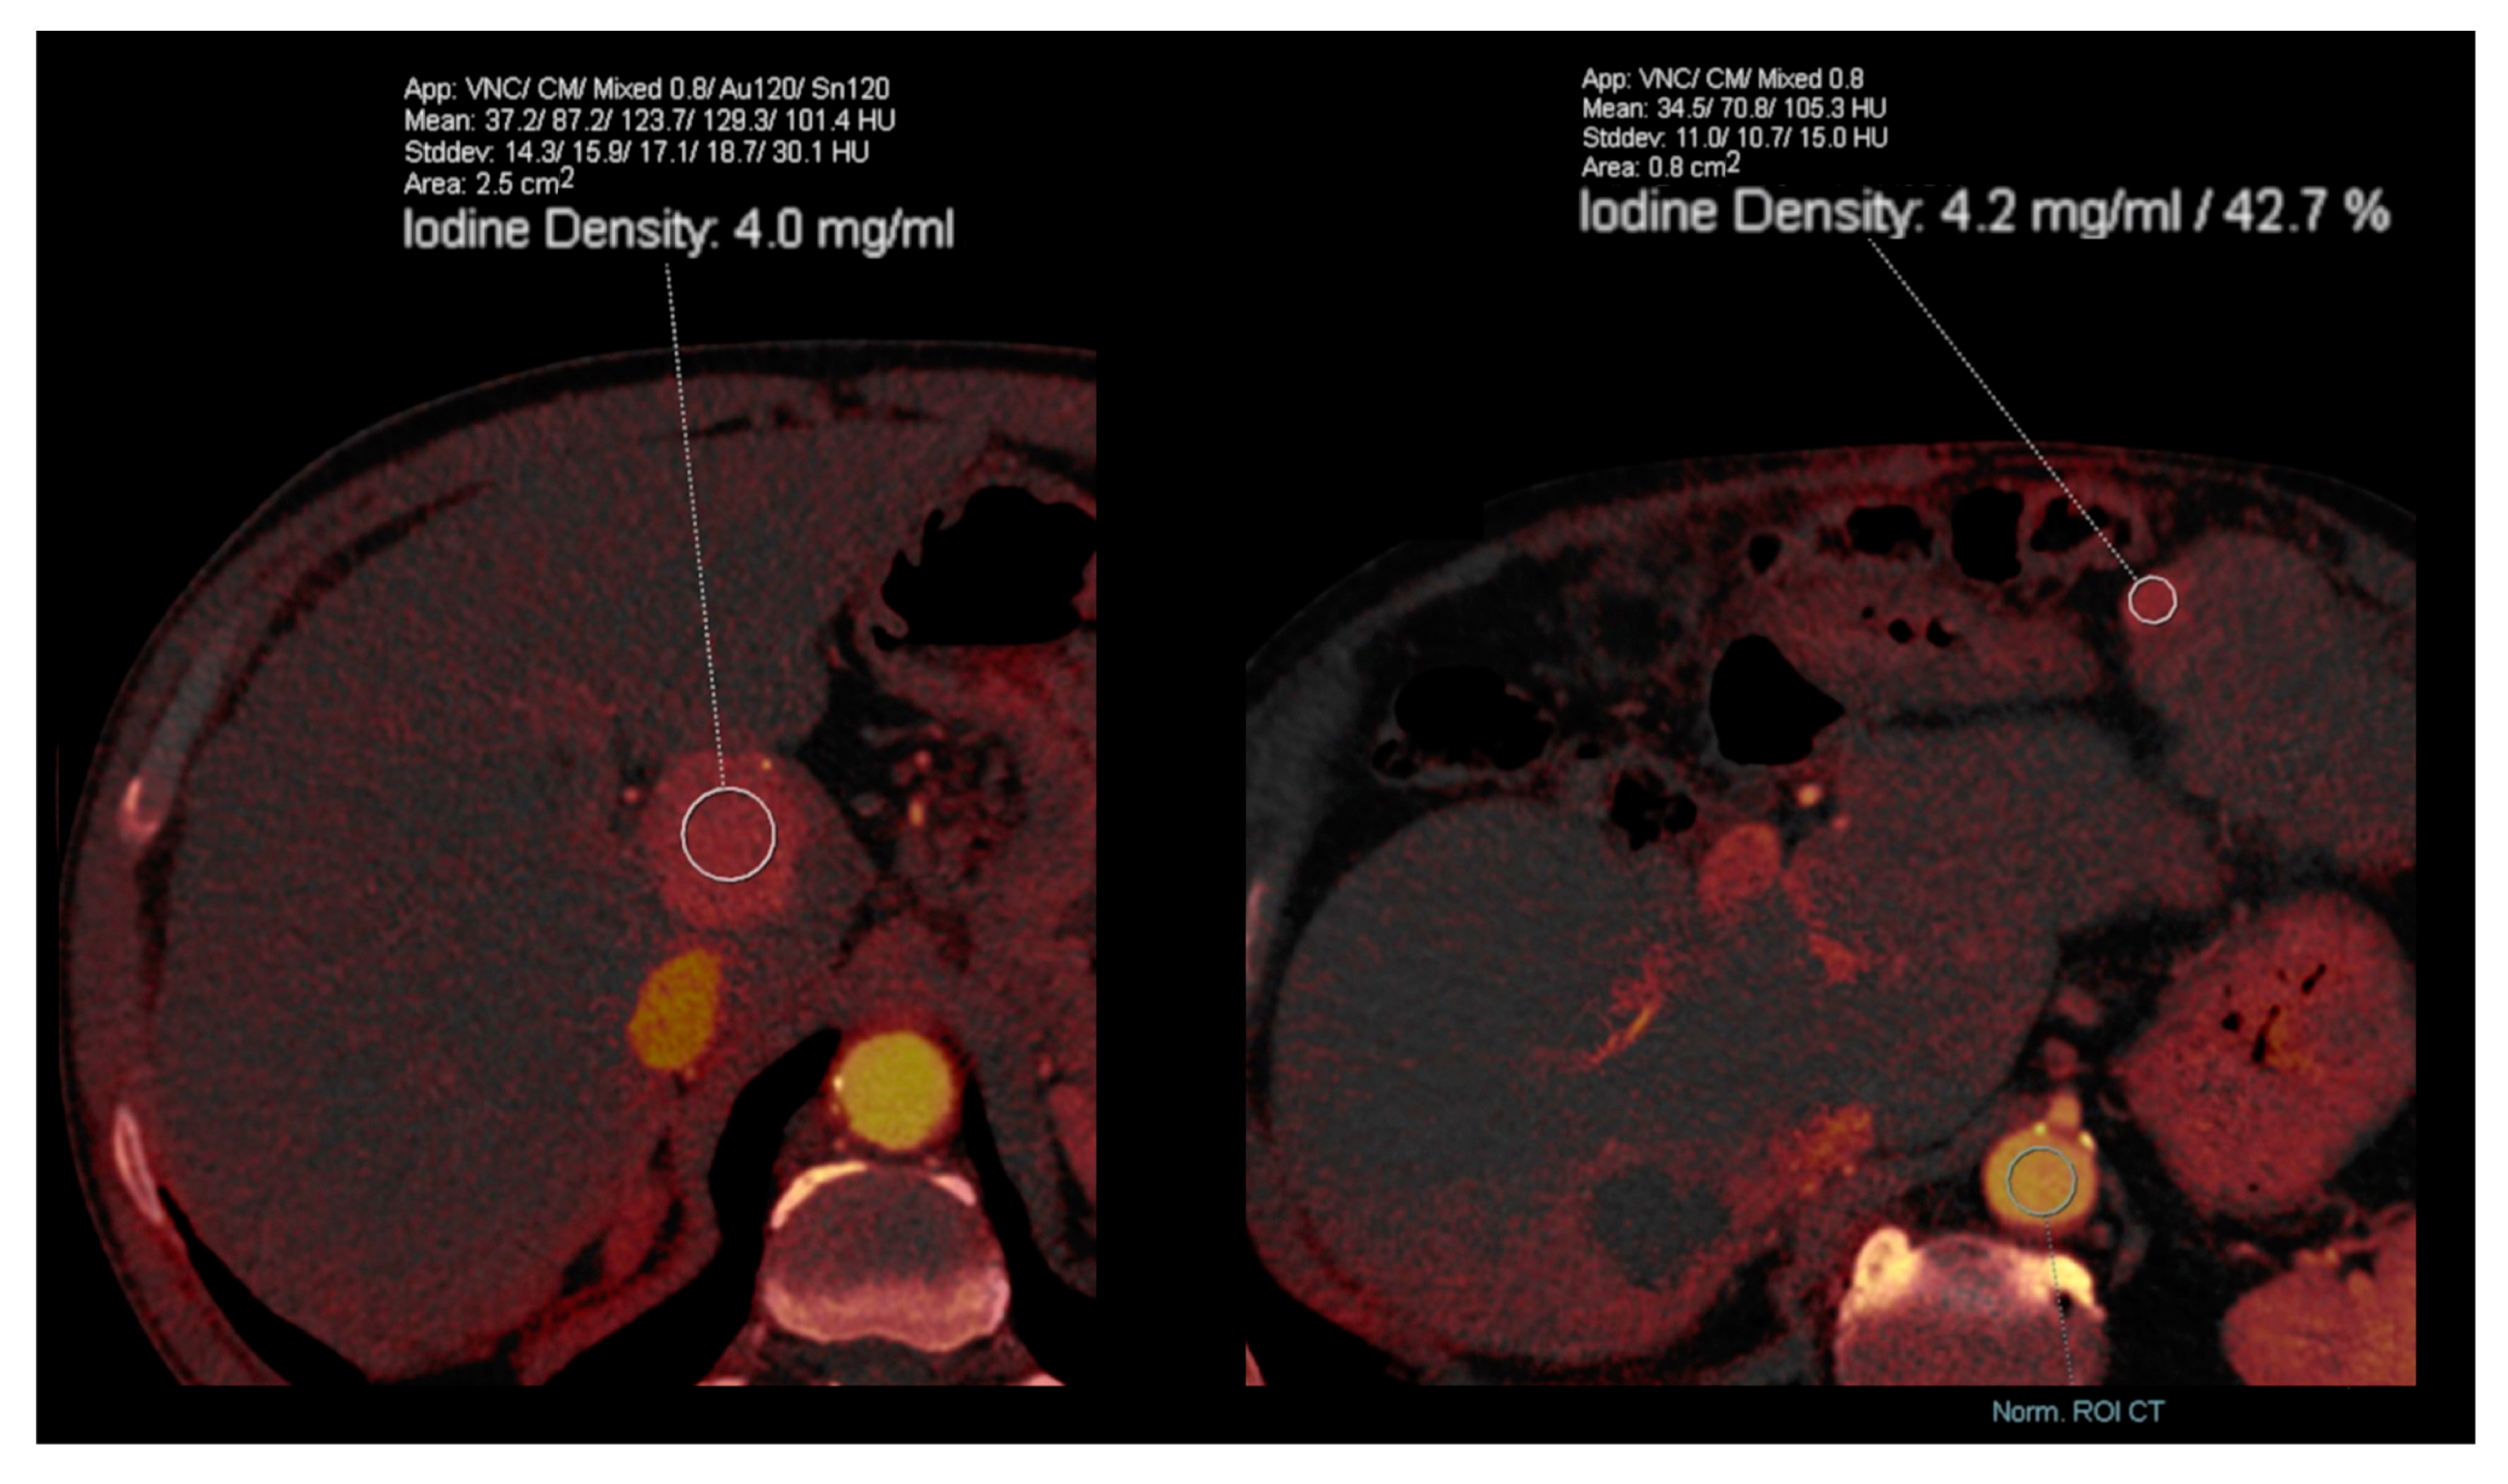

- Yang, C.B.; Zhang, S.; Jia, Y.J.; Yu, Y.; Duan, H.F.; Zhang, X.R.; Ma, G.M.; Ren, C.; Yu, N. Dual energy spectral CT imaging for the evaluation of small hepatocellular carcinoma microvascular invasion. Eur. J. Radiol. 2017, 95, 222–227. [Google Scholar] [CrossRef]

- Lewin, M.; Laurent-Bellue, A.; Desterke, C.; Radu, A.; Feghali, J.A.; Farah, J.; Agostini, H.; Nault, J.-C.; Vibert, E.; Guettier, C. Evaluation of perfusion CT and dual-energy CT for predicting microvascular invasion of hepatocellular carcinoma. Abdom. Radiol. 2022, 47, 2115–2127. [Google Scholar] [CrossRef]

- Kim, T.M.; Lee, J.M.; Yoon, J.H.; Joo, I.; Park, S.-J.; Jeon, S.K.; Schmidt, B.; Martin, S. Prediction of microvascular invasion of hepatocellular carcinoma: Value of volumetric iodine quantification using preoperative dual-energy computed tomography. Cancer Imaging 2020, 20, 60. [Google Scholar] [CrossRef]

- Luo, N.; Li, W.; Xie, J.; Fu, D.; Liu, L.; Huang, X.; Su, D.; Jin, G. Preoperative normalized iodine concentration derived from spectral CT is correlated with early recurrence of hepatocellular carcinoma after curative resection. Eur. Radiol. 2021, 31, 1872–1882. [Google Scholar] [CrossRef]